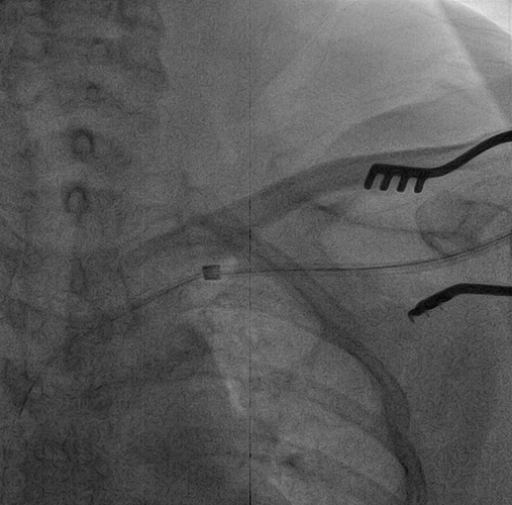

患者75岁老年女性,因“反复胸闷气促多年”确诊为扩张型心肌病,完全性左束支传导阻滞(QRS波160ms),心功能不全(EF 30.4%),曾在当地医院接受传统心脏再同步化除颤器(CRT-D)植入。术后患者胸闷气促仍反复发作,至本院就诊时心电图起博后QRS波宽度180ms,心脏超声显示左室内收缩不同步SPWMD 391ms,多巴酚丁胺试验提示心脏功能可。患者心肌NT-proBNP明显升高为2790 pg/mL。起博器程控提示CRTD能源近耗竭,冠状窦左室导线阈值过高(5V/1.2ms)。锁骨下静脉造影提示患者左锁骨下静脉近中段闭塞。面对挑战,心内科潘小宏主任医师在临时起搏保护下局麻下切开原脉冲发生器囊袋,分离原起博和ICD导线后以锁定钢丝和扩张鞘顺利拔出左心室电极导线和心室导线,剪去ICD导线头端,暴露内芯,植入锁定钢丝至接近ICD电极头端,沿锁定钢丝及电极导线扩张鞘前行至锁骨下静脉中段后难以继续推进,改为置入准分子激光鞘管,在X线透视指引下逐渐前行将ICD导线和粘连的左锁骨下静脉分离,直至上腔静脉和右心房上部,顺利拔除ICD电极导线,留置准分子激光鞘外鞘,沿鞘管置入两根泥鳅导丝,撤出准分子激光鞘外鞘。沿导丝植入7F长鞘管,根据标测到的希氏束位点及多导联心电监测图形,在希氏束315鞘指引下植入3830电极导线至左束支区城,此时测量QRS 波群宽度为112ms,阻抗感知國值等参数均良好,固定电极导线,将心房导线电极植入右心耳处。